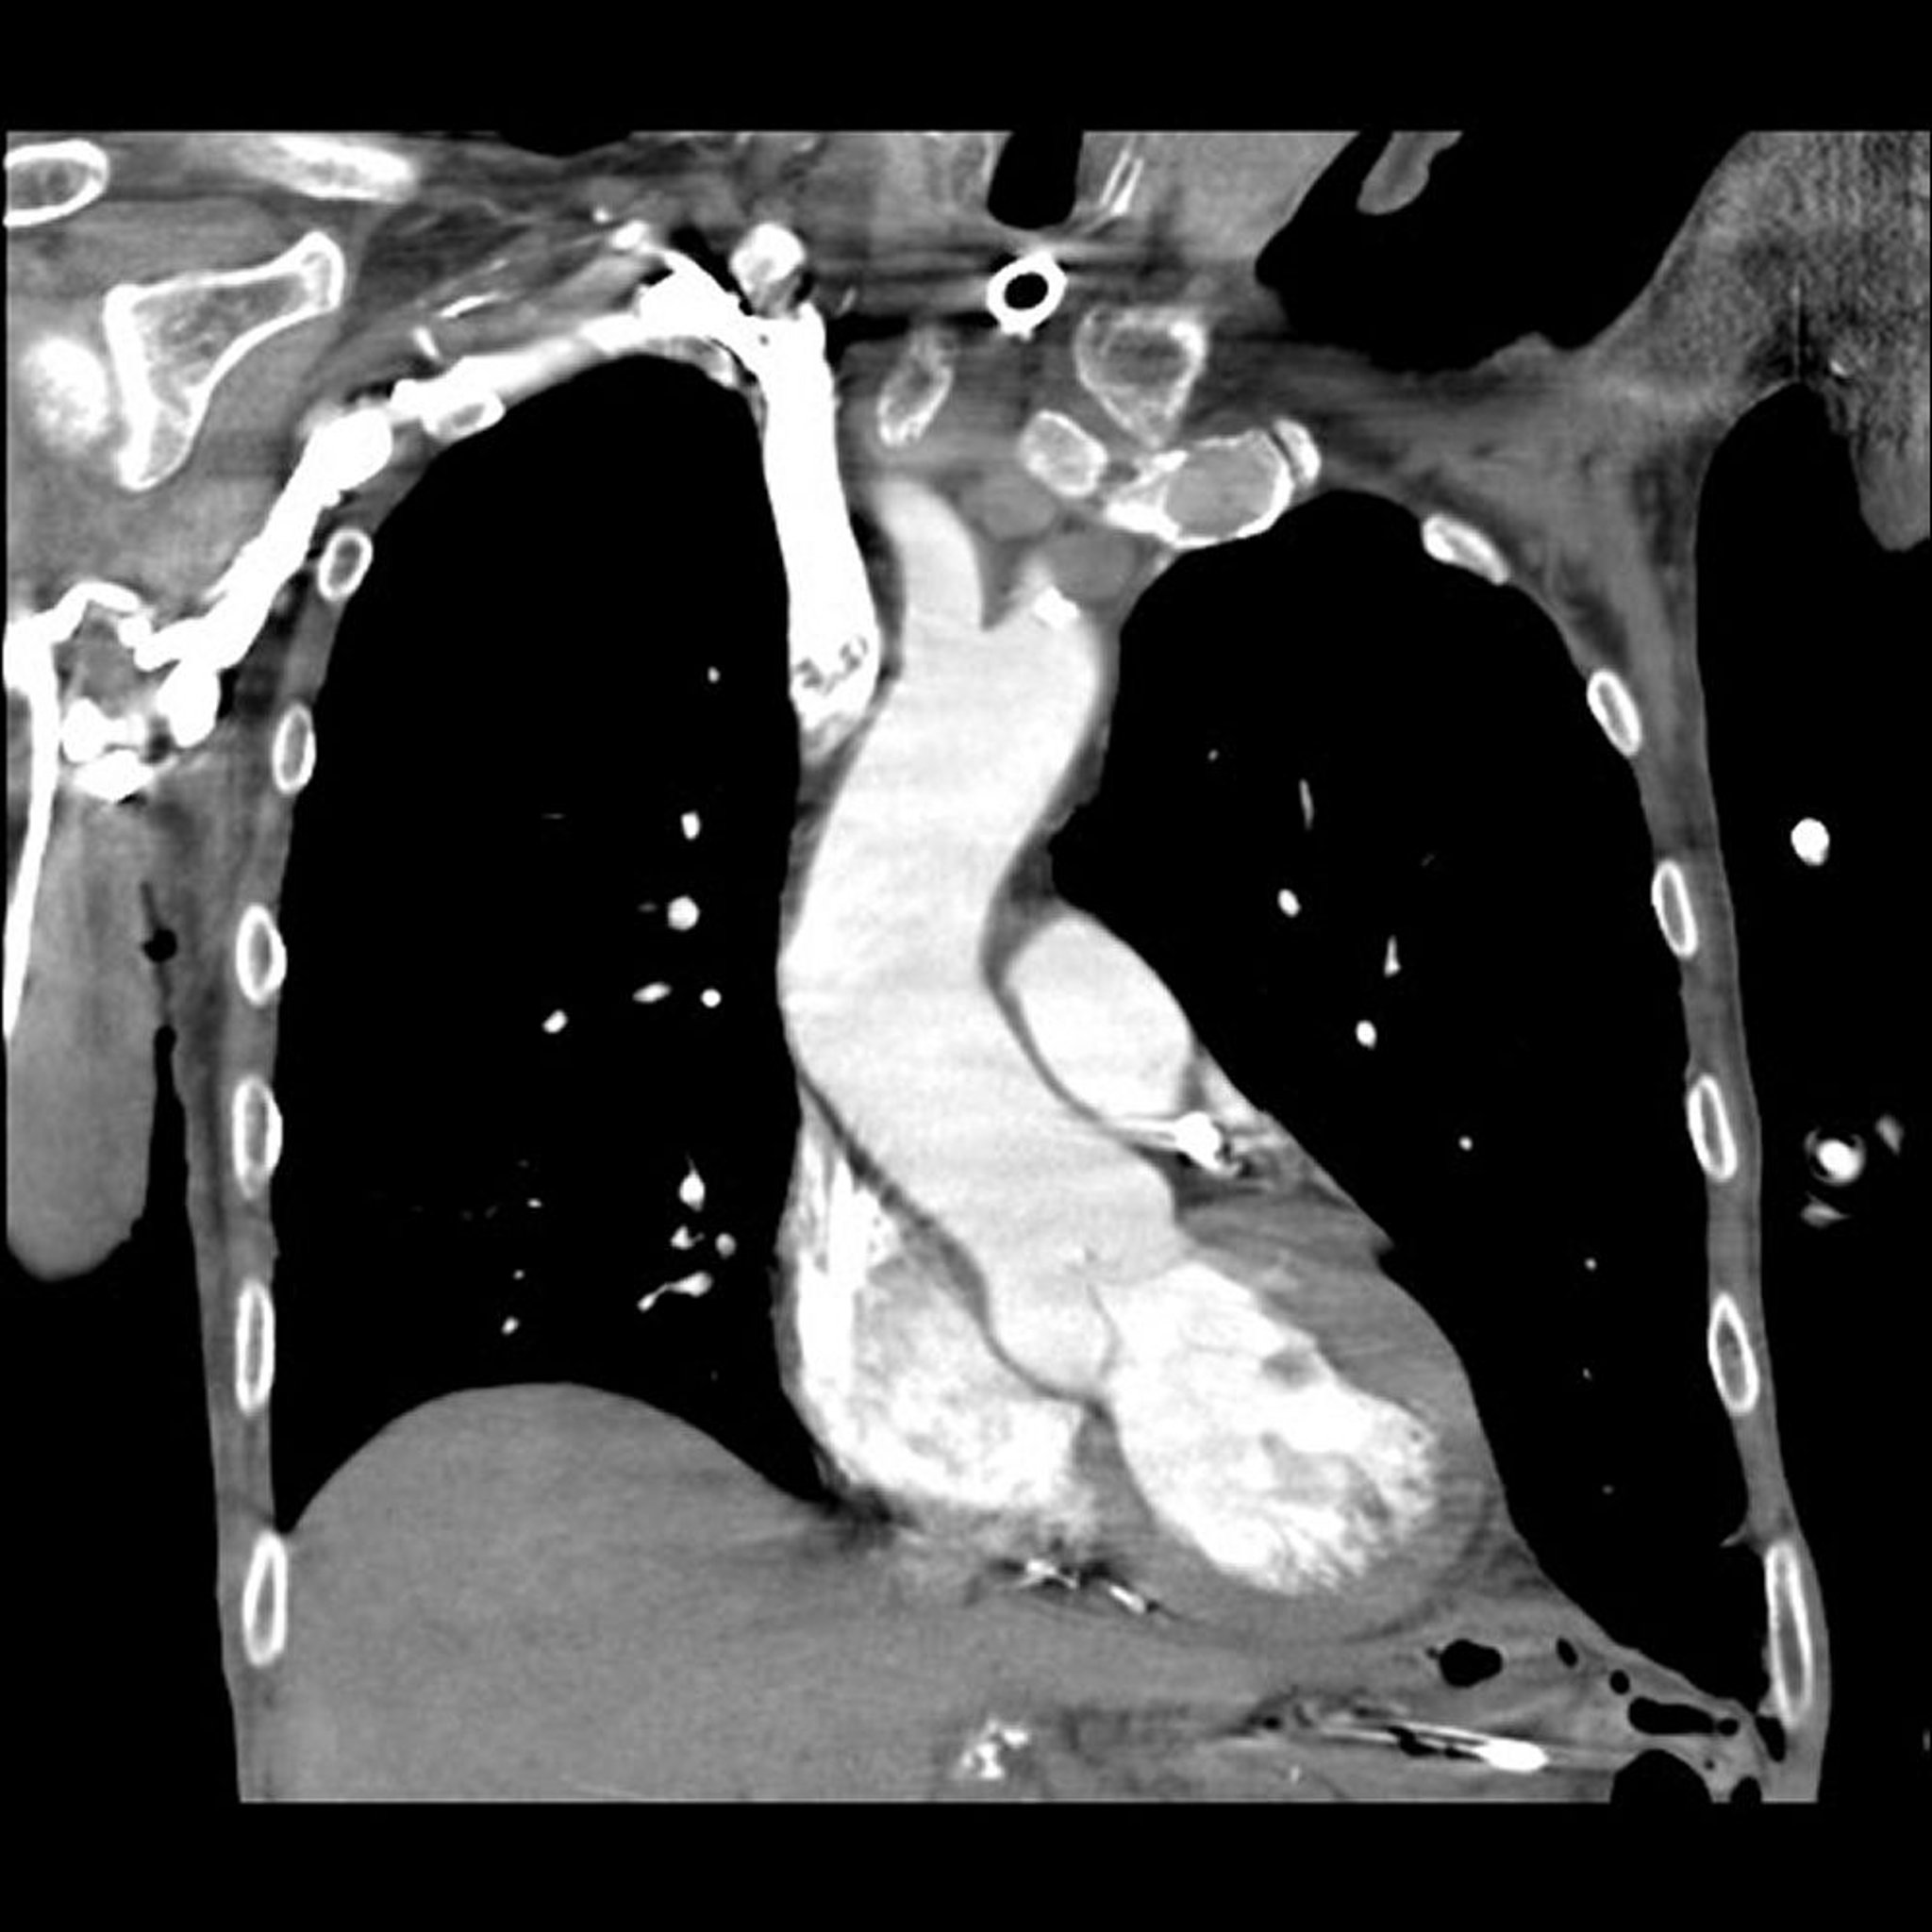

Компьютерная ангиография (КТ-ангиография) легочной артерии

Снимок предоставлен д-ром Мехметом Коцак (Mehmet Kocak).